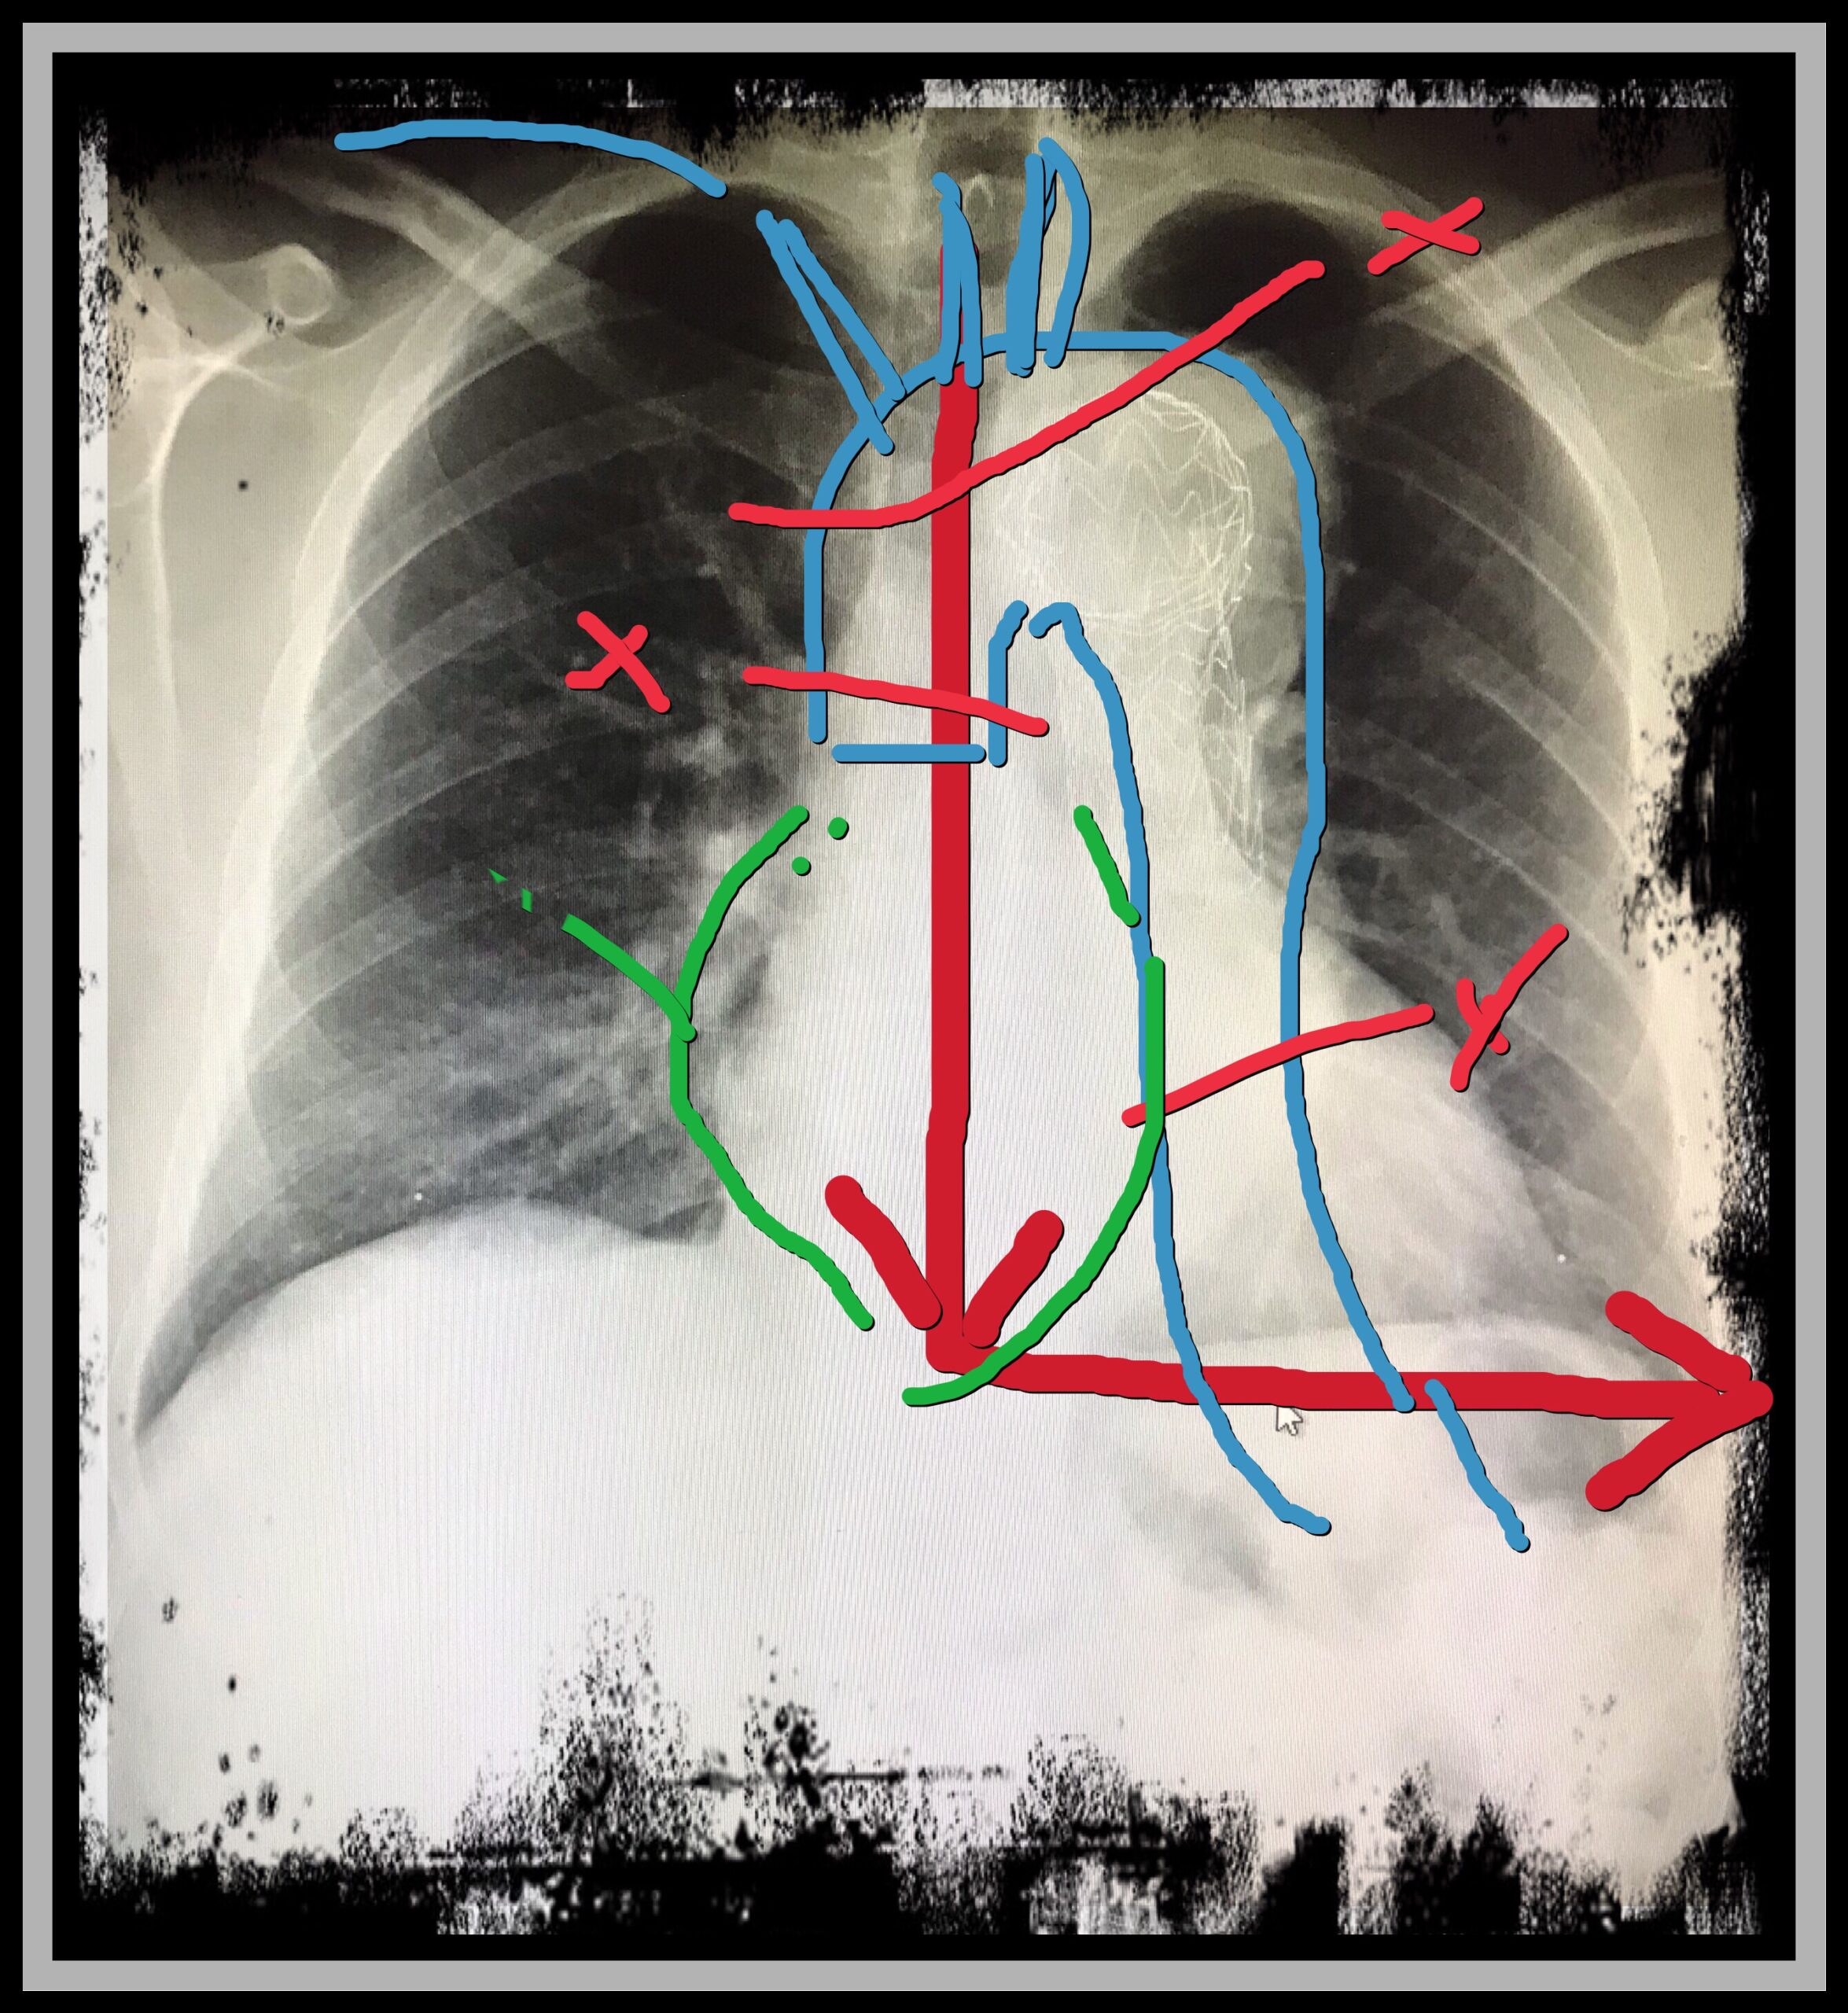

operatie plan